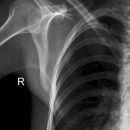

Schulter a.p. (Schultergelenk nach Grashey)

Patient steht mit dem Rücken am Stativ, gesunde Seite um 45° anheben, kranke Seite liegt auf, Arm der aufzunehmenden Seite leicht abgespreizt, Hand in Supination (Handinnenfläche zeigt von der Kassette weg). Kopf zur Gegenseite drehen lassen.

Senkrecht in Gelenkspalt bei Format 18/24.

Bei Format 24/30 oberer Kassettenrand: 2 Querfinger oberhalb der Schulter, prox. Humerus mit in der Einblendung.

Gelenkfläche der Scapulapfanne (Glenoidal-Gelenk) soll strichförmig abgebildet sein, der Humerus soll frei projiziert werden. Die Aufnahme kann mit der Rockwood-Aufnahme kombiniert werden (Röhrenkippung). evtl. Schulterfilter verwenden.

- vollständige überlagerungsfreie Darstellung des Humeruskopfes und des Gelenkes

Bei Fragen im Subacromial-Raum sollte dieser überlagerungsfrei dargestellt werden.